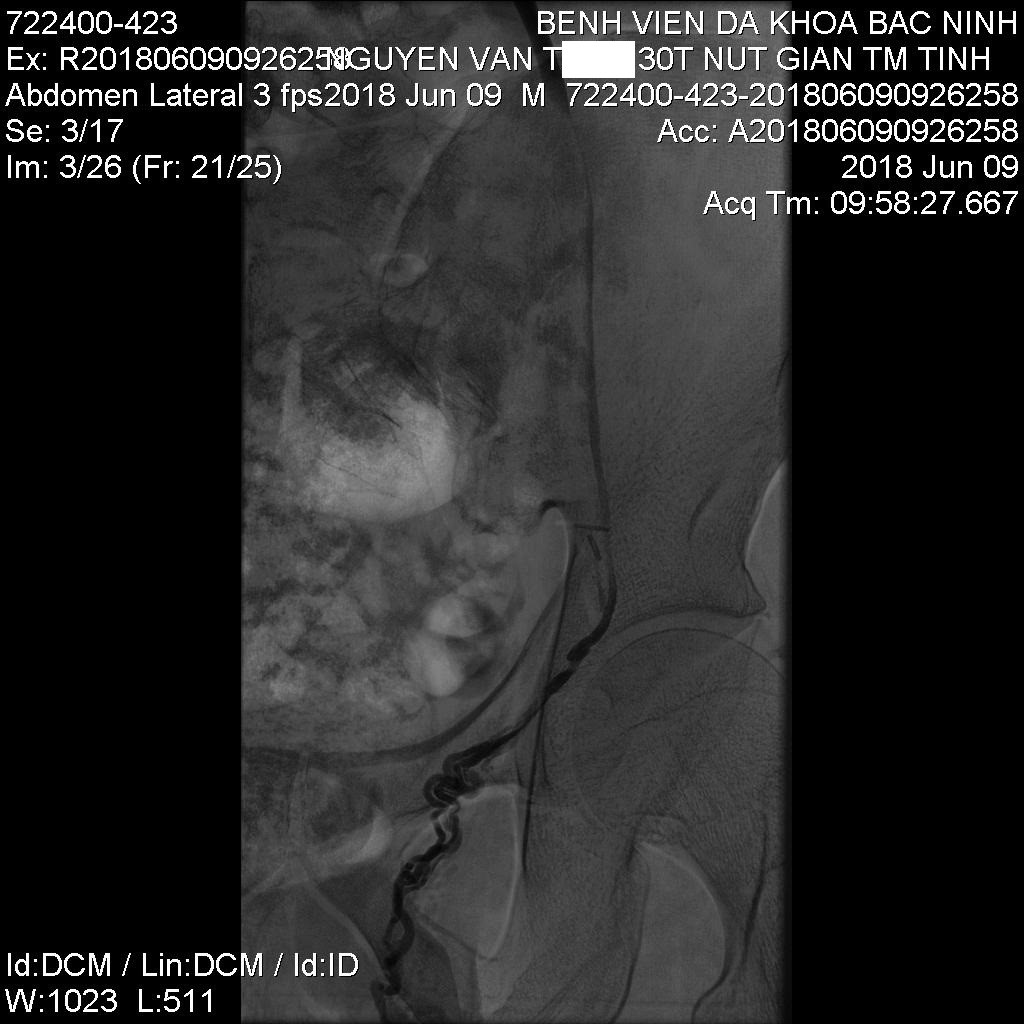

![]() Trước can thiệp |

Kỹ thuật này có nhiều ưu điểm như phương pháp vô cảm gây tê tại chỗ dưới da, bệnh nhân hoàn toàn tỉnh trong quá trình can thiệp. Đây là phương pháp can thiệp xâm lấn tối thiểu vào mạch máu bệnh nhân qua duy nhất một dụng cụ mở đường vào tĩnh mạch rộng khoảng 2mm, thông thường vị trí tiếp cận là tĩnh mạch đùi chung bên phải. Sau đó, bác sỹ can thiệp sẽ luồn các loại ống thông và dây dẫn vào trong tĩnh mạch thận trái và tĩnh mạch tinh trái, chụp hình mạch máu dưới máy số hóa xóa nền để đánh giá hình thái, các loại biến đổi giải phẫu và huyết động học tĩnh mạch tinh trái. Sau khi đánh giá được toàn bộ hình thái và động học của các tĩnh mạch tinh giãn, bác sỹ can thiệp lựa chọn vật liệu nút mạch phù hợp để đảm bảo tắc toàn bộ các nhánh tĩnh mạch tinh trái giãn có dòng trào ngược. Thời gian can thiệp ngắn, trung bình 60 – 90 phút kể từ lúc người bệnh vào phòng can thiệp. Sau can thiệp, các loại ống thông được rút bỏ và băng ép vị trí mở đường vào tĩnh mạch đùi, bệnh nhân có thể đi lại bình thường sau 4 giờ can thiệp, có thể xuất viện 1 ngày sau thiệp.